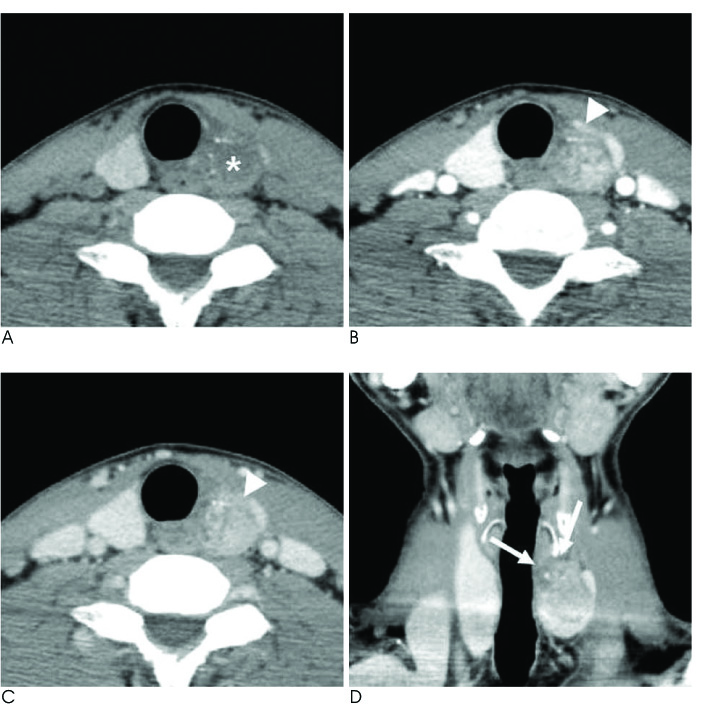

The purpose of this study is to analyze the computed tomography (CT) features of follicular thyroid carcinoma (FTC) as compared to those of papillary thyroid carcinoma (PTC) to identify the characteristic imaging features of FTC.

There were no significant differences between the patients with FTCs and those with PTCs with respect to age and gender, and the internal composition, calcification and enhancement homogeneity of the tumor. However, the FTCs tend to show a larger size (32 mm vs. 15 mm; respectively, p < 0.001), a round to oval shape (52.9% vs. 14.8% respectively, p = 0.001), a well-defined smooth margin (58.8% vs. 14.8% respectively, p = 0.009), less extrathyroidal extension (11.8% vs. 51.9% respectively, p = 0.007) and less LN metastasis (0% vs. 29.6% respectively, p = 0.016) compared to that of the PTCs. Furthermore, the FTCs showed significantly stronger enhancement in the early phase (146.4+/-42.4 vs. 98.5+/-38.2 respectively, p < 0.001) and a greater decrement of the late enhancement (-44.6+/-25.2 vs. -18.7+/-27.9 respectively, p = 0.003) compared to that of the PTCs.

FTCs had a tendency to be observed on neck CT as well-defined, smooth, round to oval nodules with strong early enhancement and a definite decrement of late enhancement as compared to the PTCs.